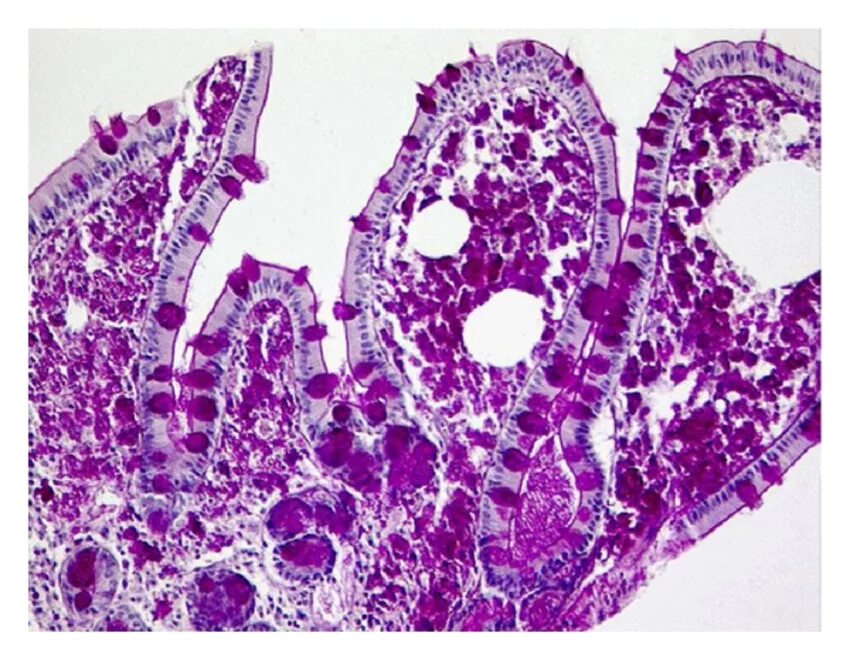

Гистологические заболевания